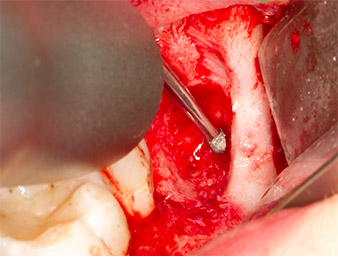

To expose the root remnant with as little trauma as possible to the tissue, a further instrument was used (Piezomed S2) that is primarily indicated for preparing the lateral window in augmentations of the sinus floor. The diamond-coated ball was additionally used to smooth sharp bone edges (Fig. 6 and 7). All the Piezomed attachments were used with the relevant automatic default setting without booster function.

Using an instrument for periodontal debridement (Piezomed P1), the periodontal ligament space of the radix relicta was then widened minimally (Fig. 8).

The same activated instrument was inserted into the root canal and loosened the fragment as a result of its micro-oscillating vibrations (Fig. 9, 10).